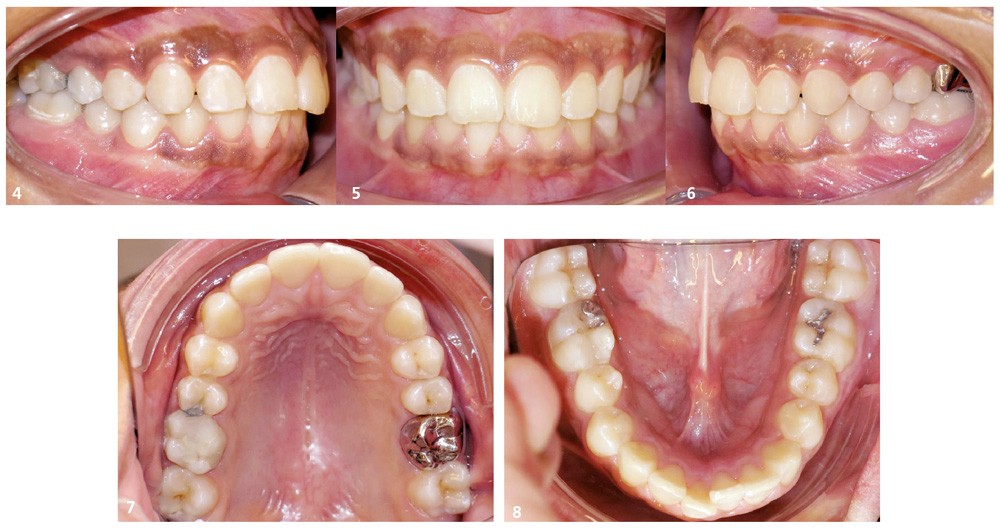

Le parodonte est épais mais une récession gingivale débutante est notable au niveau de 41 et s’accompagne d’une proéminence radiculaire au niveau mandibulaire, liée à la pro-alvéolie incisive. L’hygiène est correcte, ce qui ne fut pas le cas précédemment : la patiente présente des légères taches diffuses de déminéralisation, et surtout des soins carieux importants sur 16 26 et 46. Par ailleurs, les arcades sont larges et symétriques et l’occlusion de classe I est satisfaisante (fig. 4 à 8).

Si l’encombrement mandibulaire est cliniquement faible (malposition incisive avec un manque de place estimé à 2 mm), nous pouvons considérer la dysharmonie dento-maxillaire (DDM) mandibulaire comme importante si l’on prend en compte l’encombrement postérieur lié à l’évolution compromise des dents de sagesse, la courbe de Spee, et si l’on souhaite repositionner l’incisive mandibulaire en proalvéolie (fig. 9).